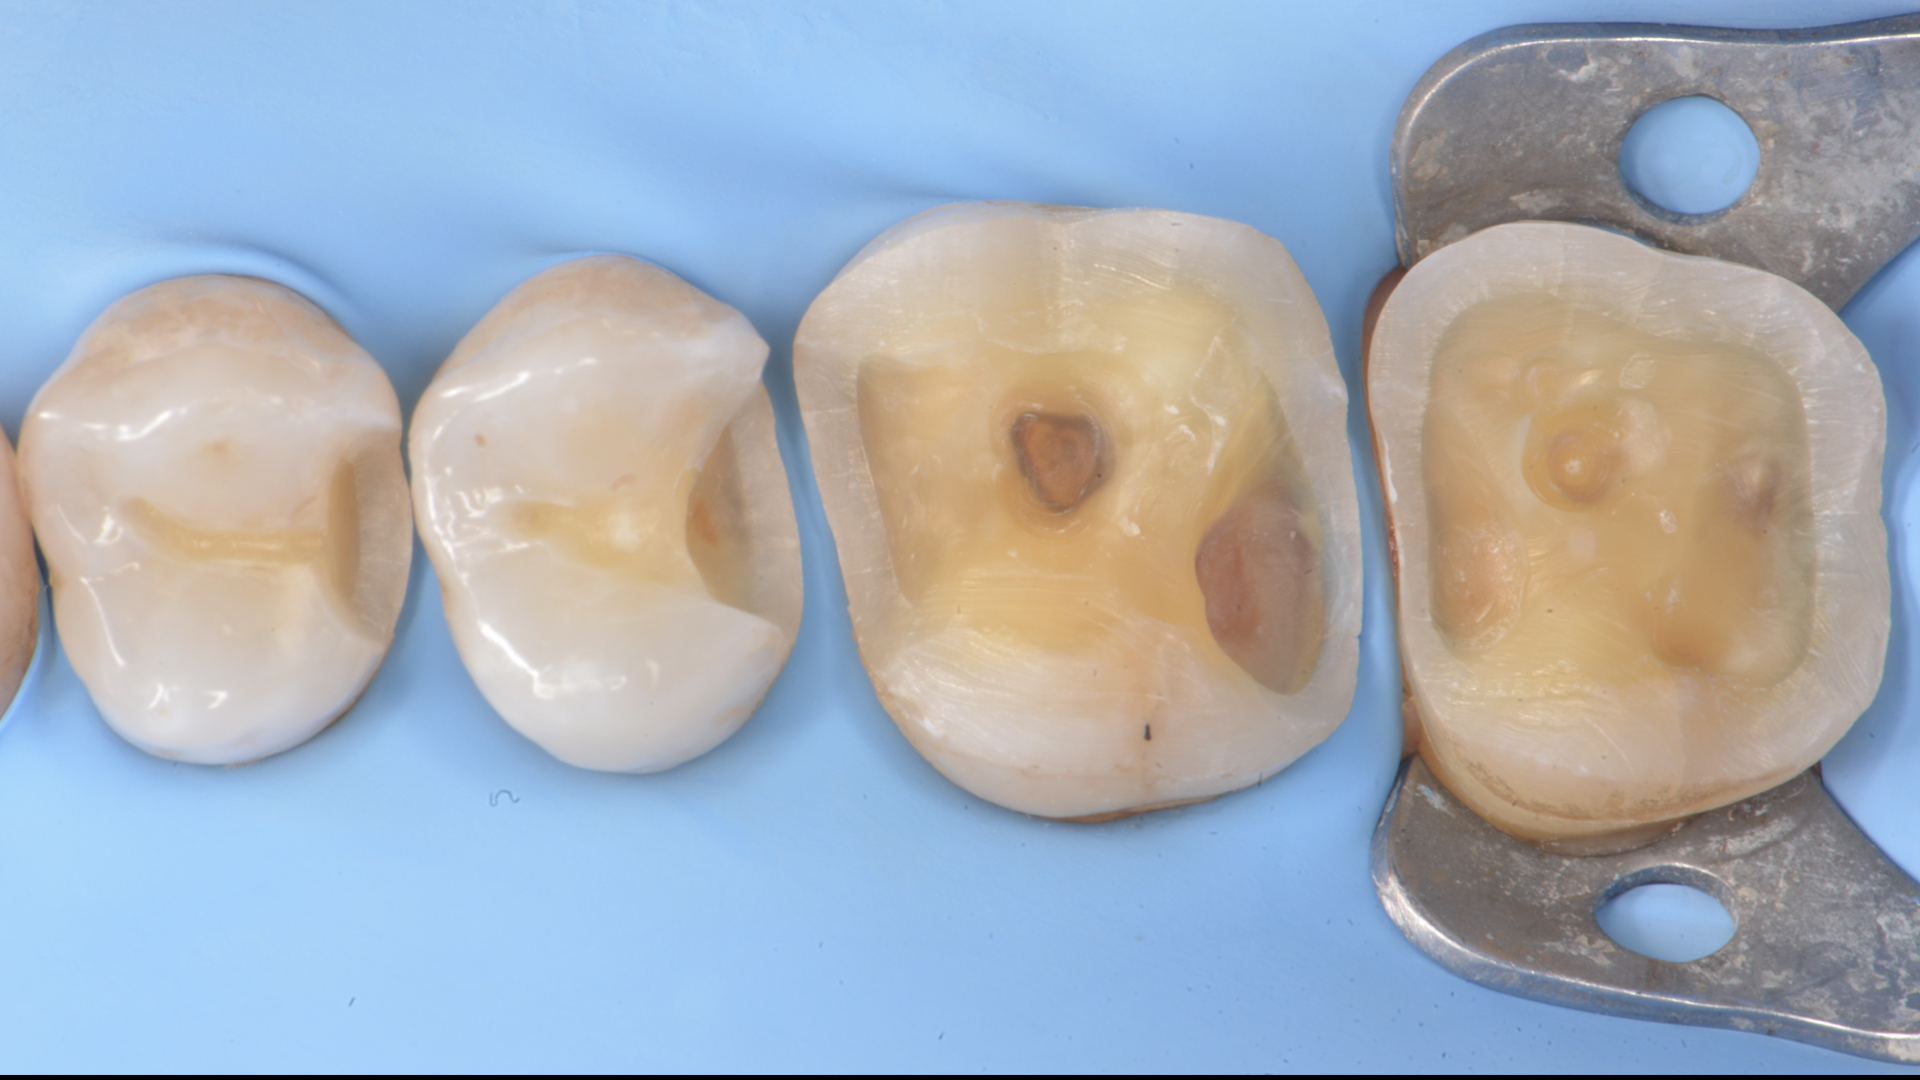

Figure 7.  Impression (Sandwich technique)Figure 8. Master cast. Hybrid Ceramic overlays. (ODT Alessandro Morelli)

Figure 9. Cleaned and sandblasted teeth prior to cementationFigure 10. Luting of the overlay 1.7 with pre heated composite